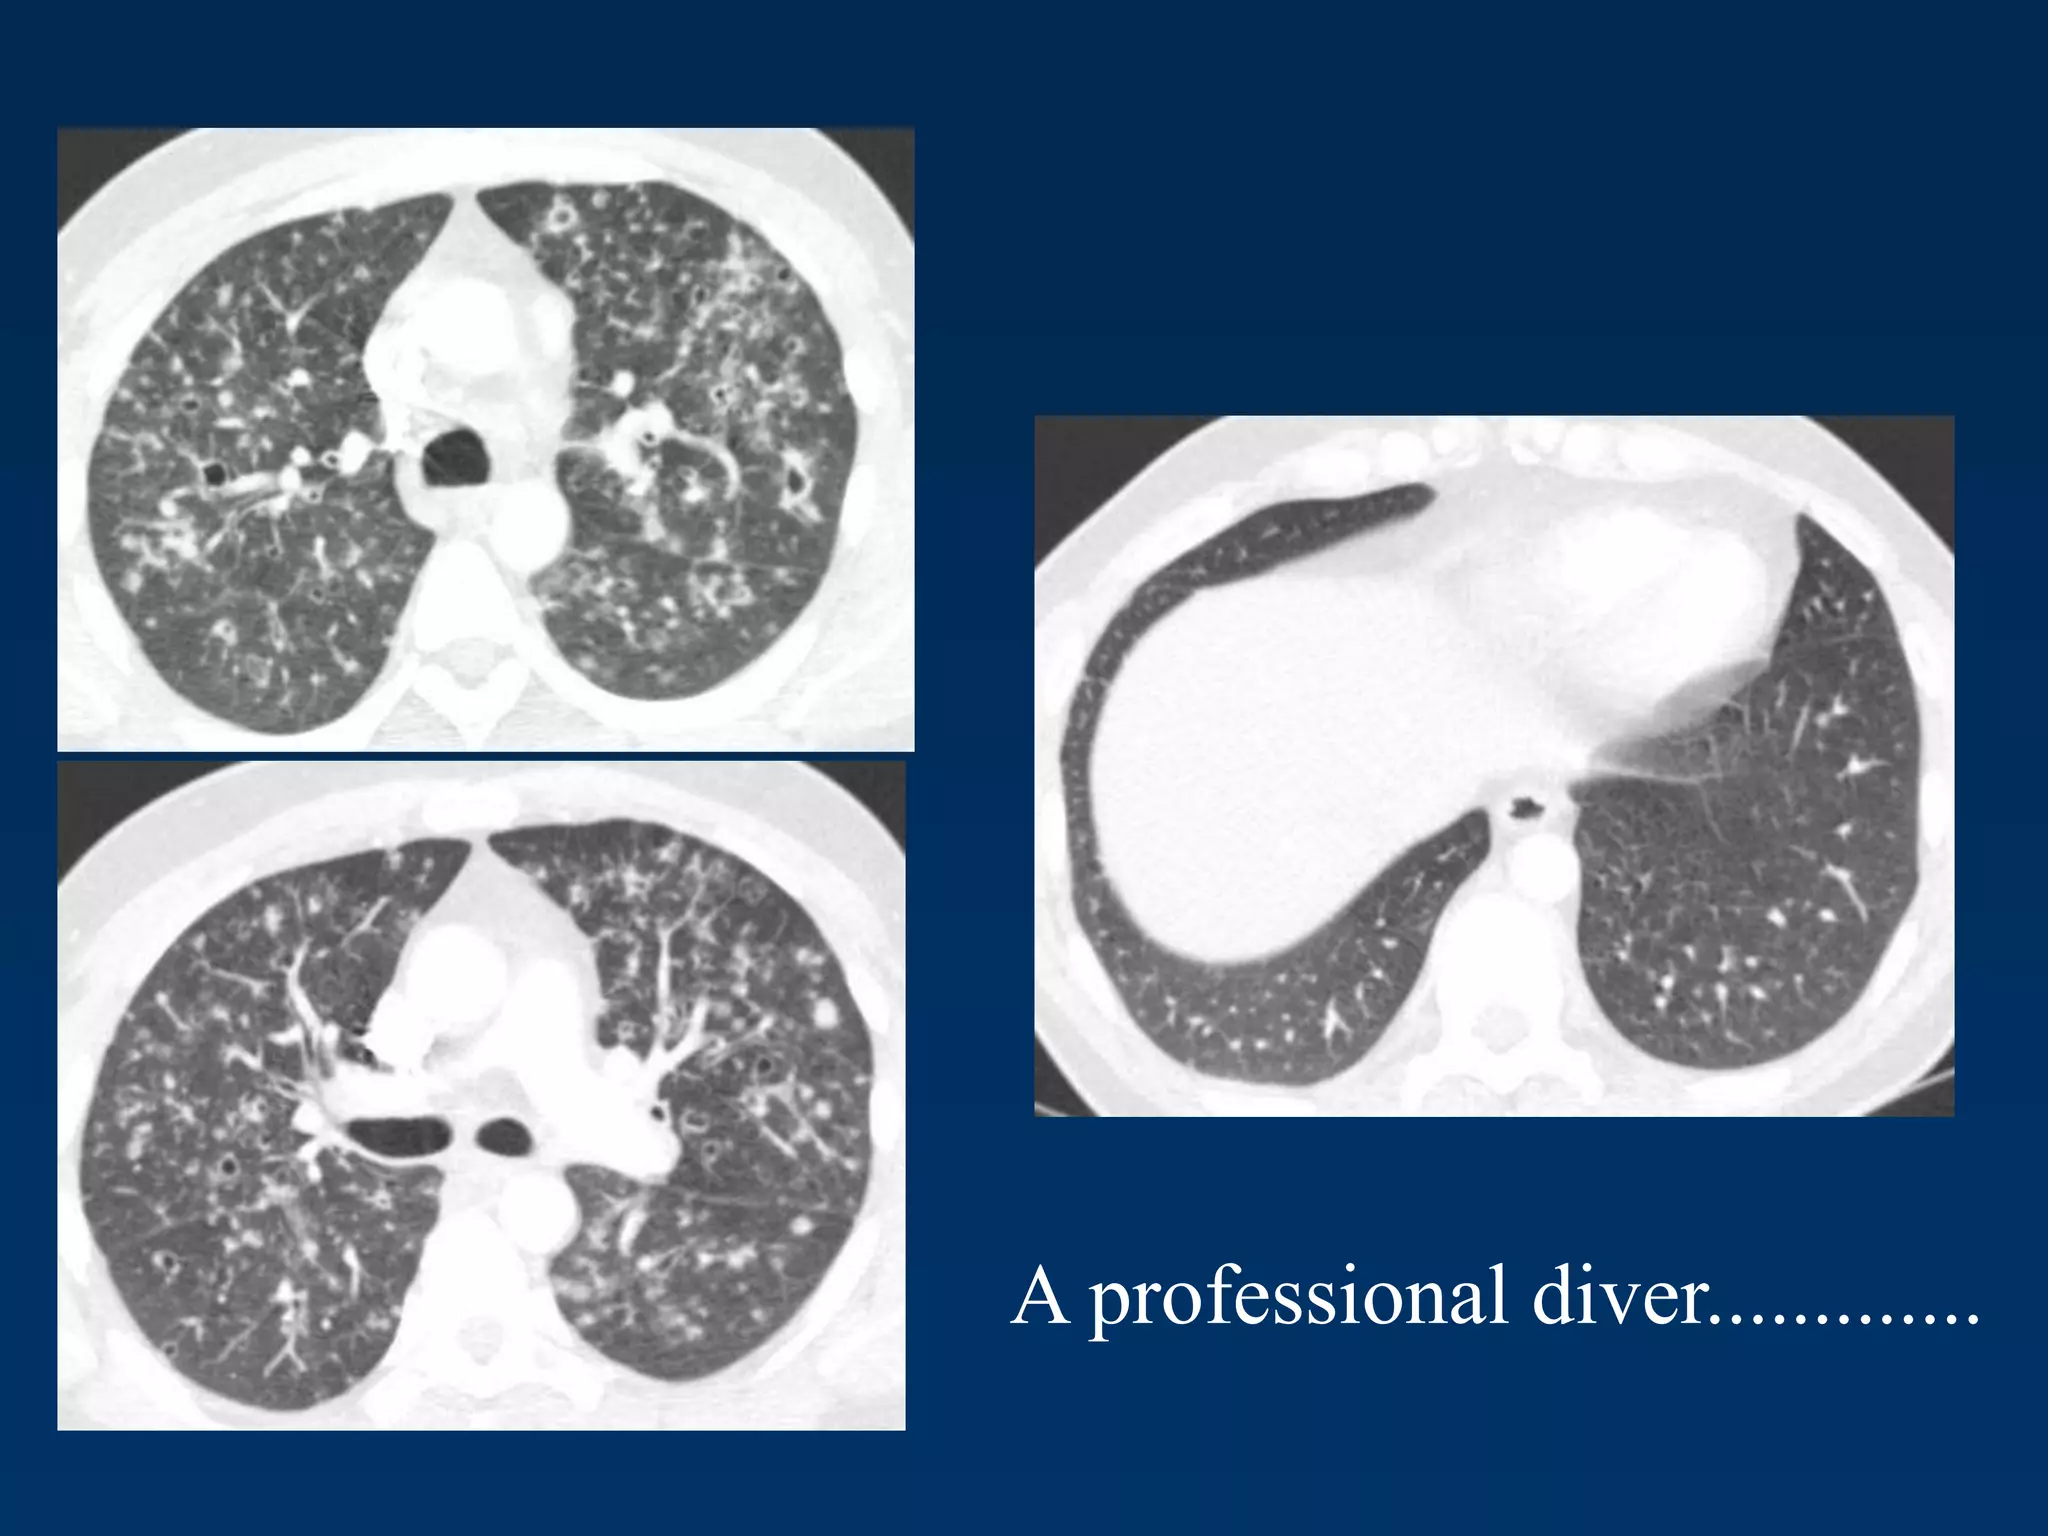

A professional diver.............

.......after cessation of smoking